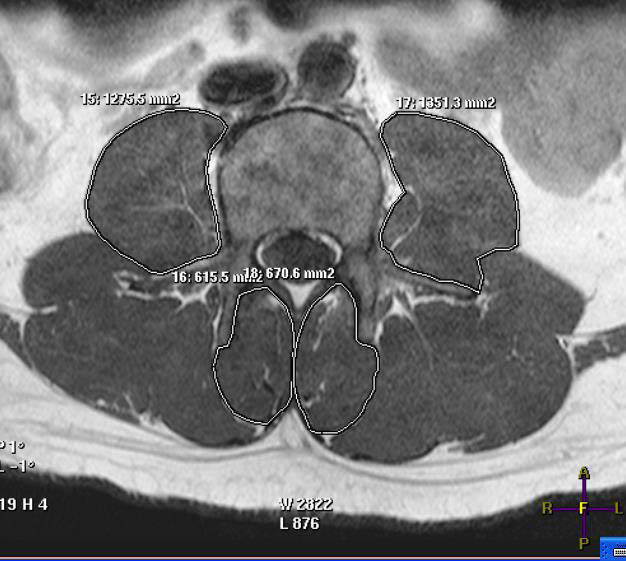

Figure 2: A measuring method of the multifidusmuscle and the major psoas muscle.

figure 2